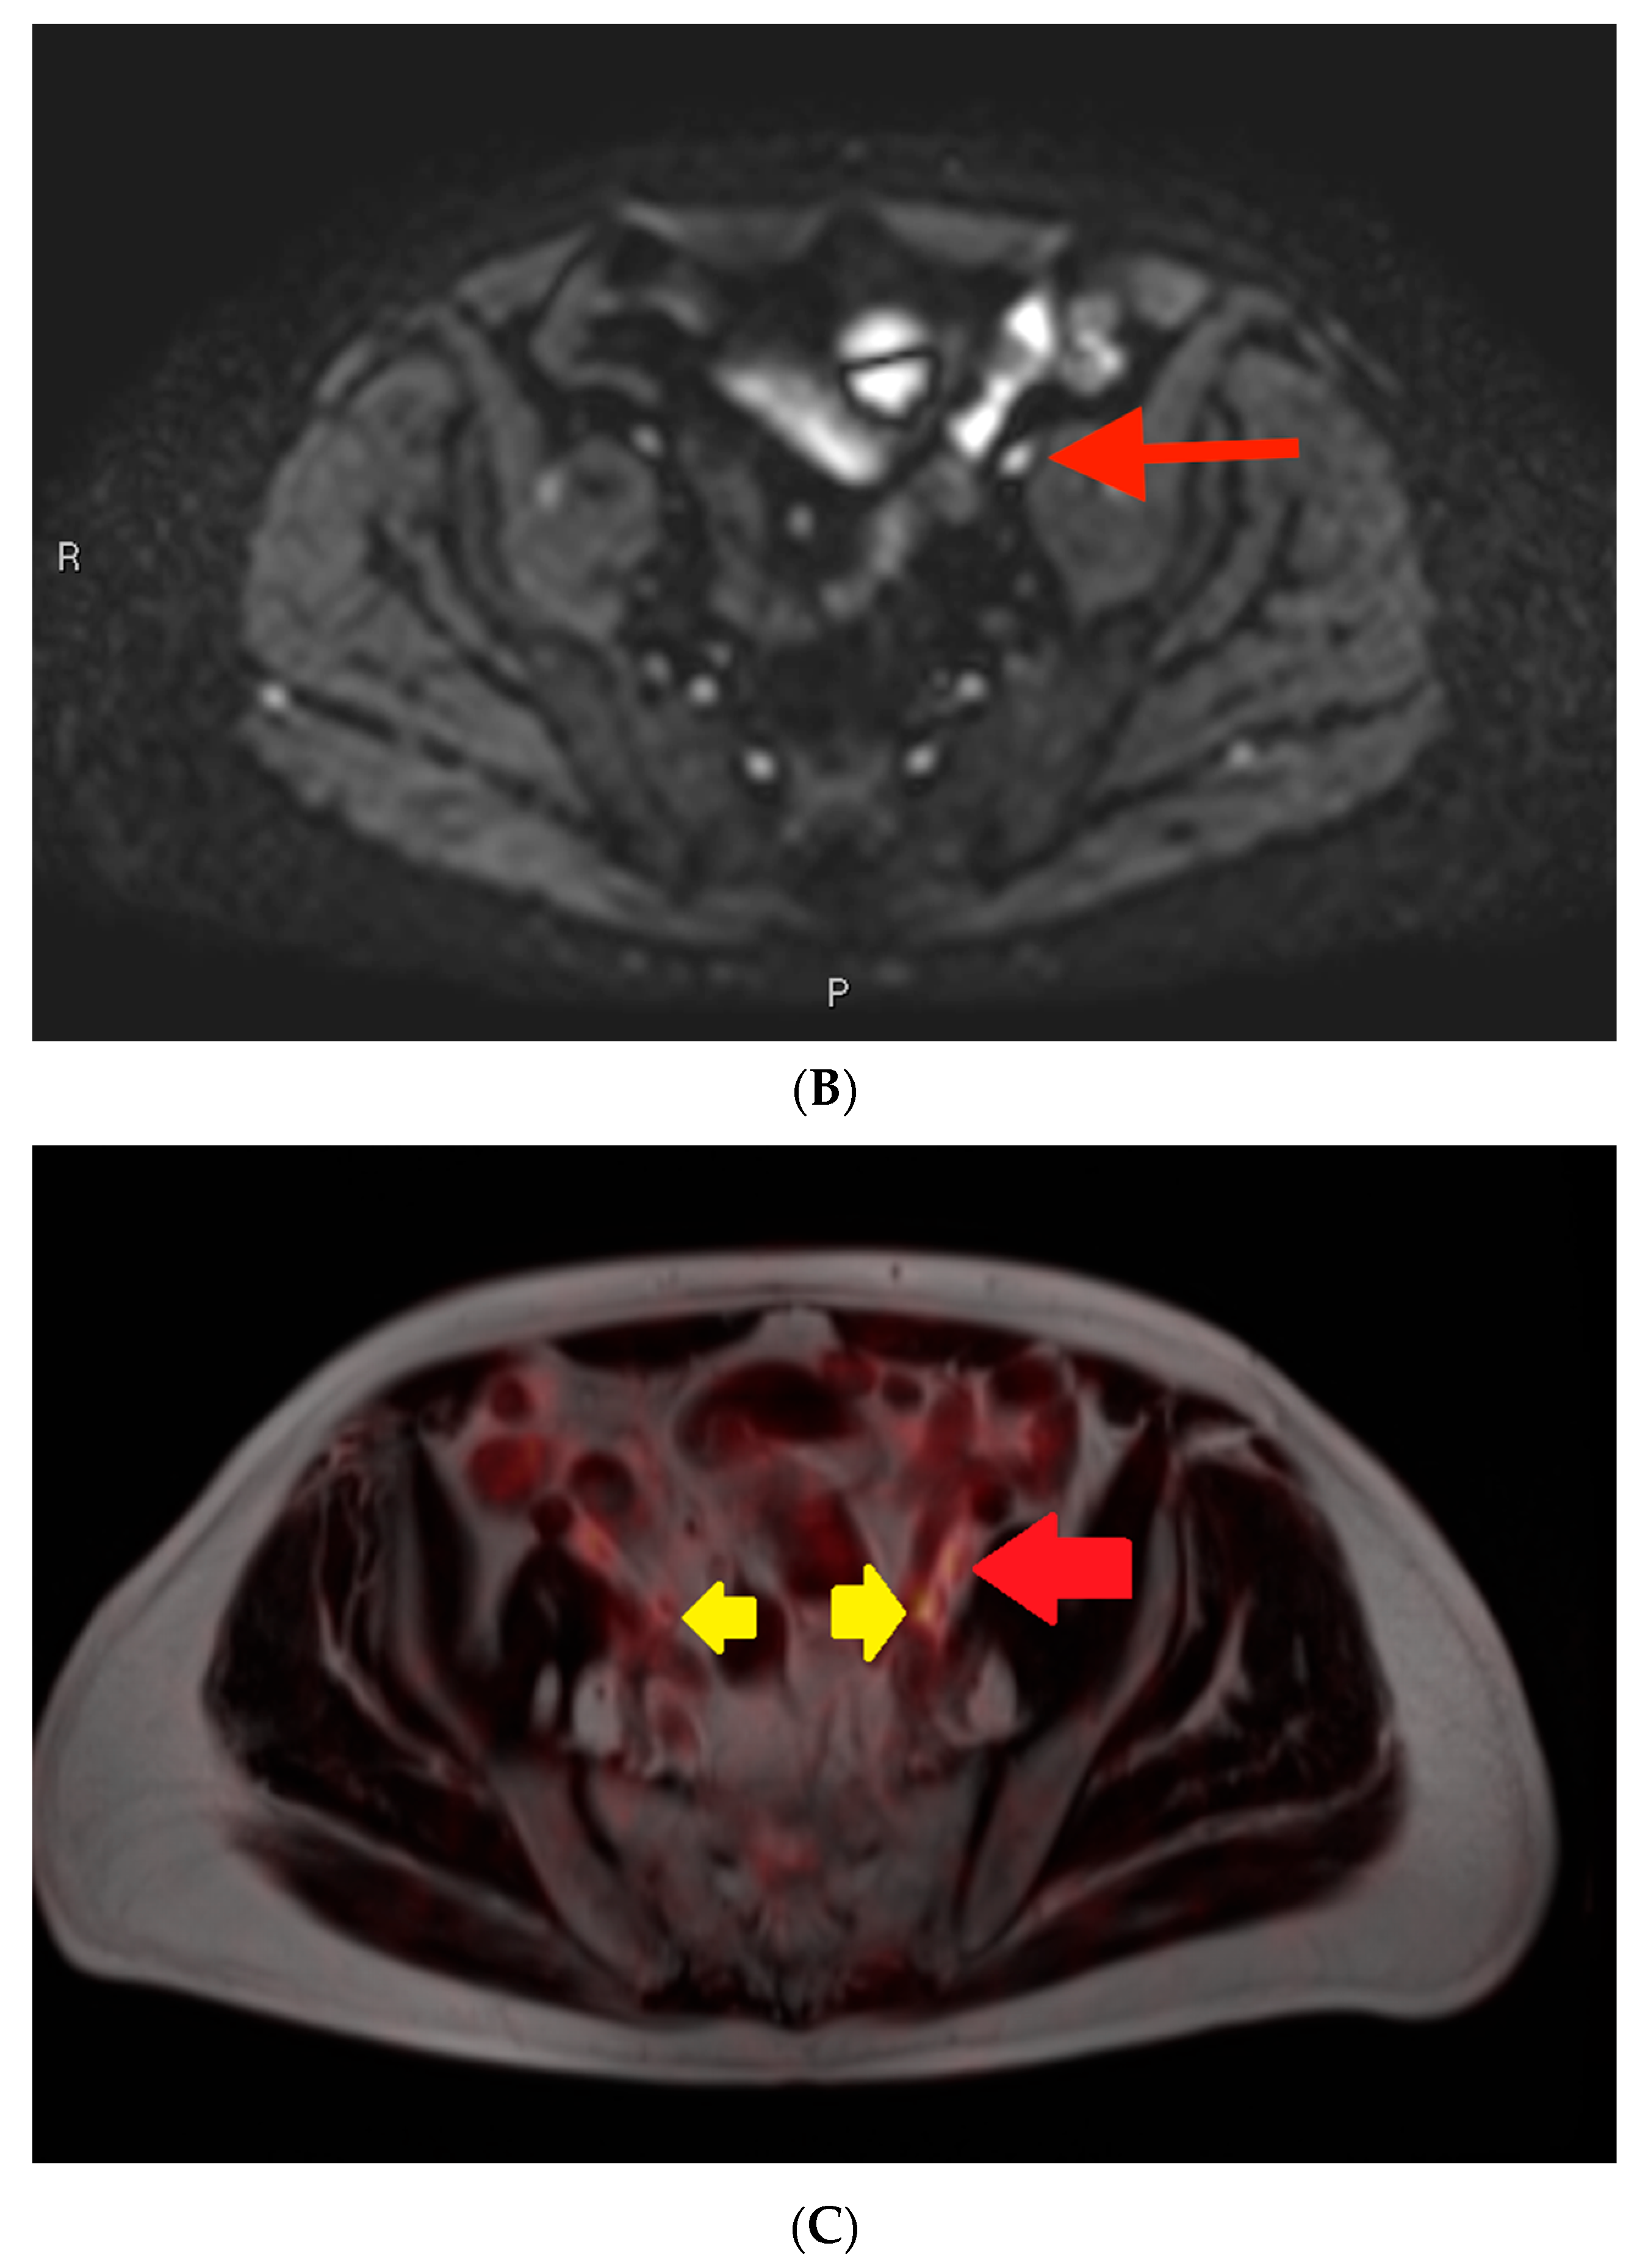

3.1. Example 1—Anatomically Normal Lymph Node Metastasis

As seen in Figure 3, the largest class, comprising half of the cases, was anatomically normal. In other words, the size and morphology of the metastatic focus did not suggest an abnormality on MRI. This description applied to many false negative cases involving lymph node metastases. In this case, the initial mpMRI was negative for the lymph node metastases by size criteria, while the PSMA PET showed a PSMA-avid, subcentimeter, left-sided lesion (Figure 3C). Detailed review of the mpMRI confirmed that the lymph node in question measured well under 1.0 cm in short axis, with a similar “cold” contralateral lymph node with essentially the same characteristics (Figure 3A,B). There were no other features in the mpMRI that were suspicious for metastatic disease.

Post-contrast fat-saturated gradient T1-weighted image (A), diffusion-weighted imaging with b = 900 s/mm2 (DWI) (B), and fused PET/single-shot T2-weighted imaging (C) through the pelvis. In Figure 3A, the lesion is marked with measurement calipers. In Figure 3B,C, the lesion is denoted with a red arrow. Yellow arrows indicate the ureters, which show physiologic PSMA PET uptake.